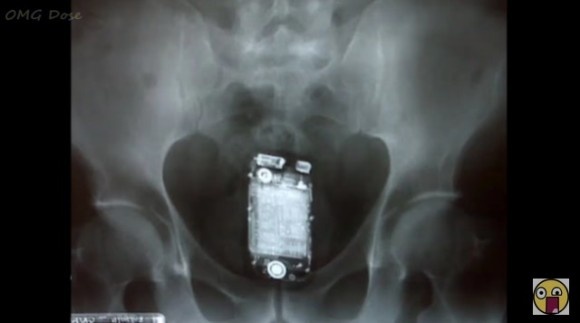

(画像)2019年、アメリカ人が体の“穴”に入れてしまった様々なモノ

2019年、アメリカ人が体の“穴”に入れてしまった様々なモノ

「2019年、アメリカ人が体の“穴”に入れてしまった様々なモノ」のページです。デイリーニュースオンラインは、

社会

などの最新ニュースを毎日配信しています。